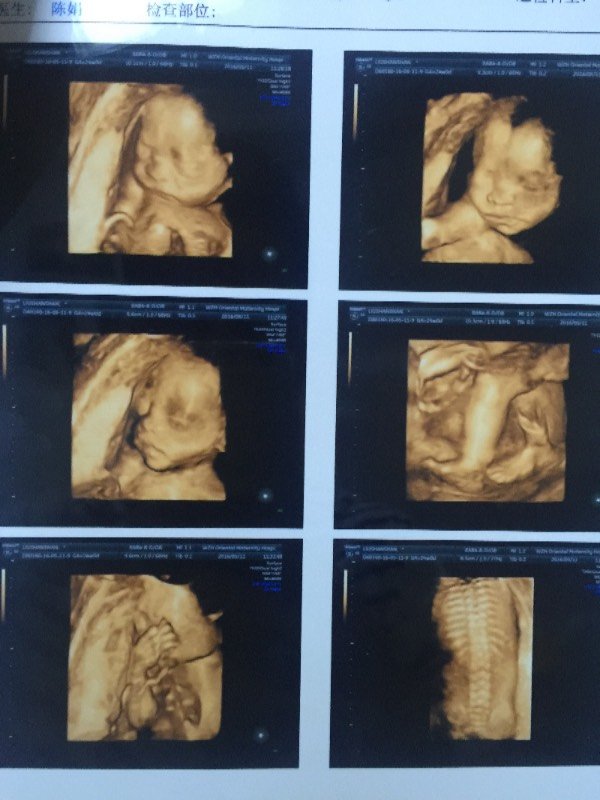

有高手能看的出下图四维彩超里的宝宝是男是女?猜中200元微信红包一个 !(留微信号或者私信) 点击展开 匿名用户 2016-05-11 22:11 为您推荐: 其他回答 哈哈 男孩 匿名用户 2016-05-11 22:12 相关问题 刚刚去照四维彩超,给医生塞了五百元红包,他告诉我是个男宝宝,宝妈们谁看得懂,请告诉我一下,由于婆婆 我在微信上认识了个女孩,骗我3千元红包,报案有用吗? 女孩情人节给我发微信红包7 77元,我该回多少呢!她最近结婚了